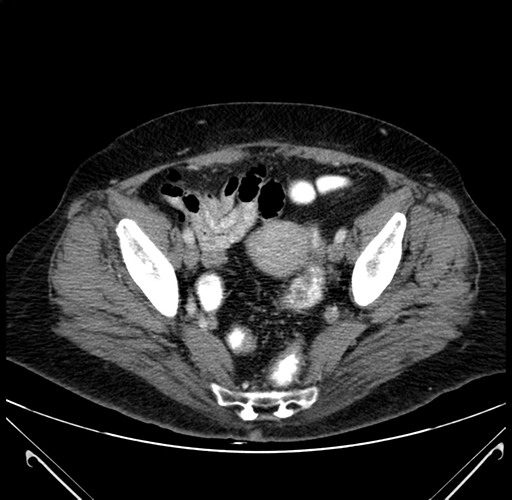

Pre-Chemo: Axial Venous

Axial Venous